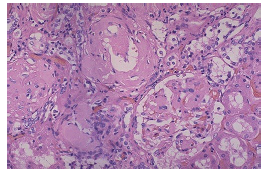

H&E slide of kidney - what does it show? What staining would you do next?

thickened vascular walls => protein deposition?

Stain with Congo Red for amyloidosis